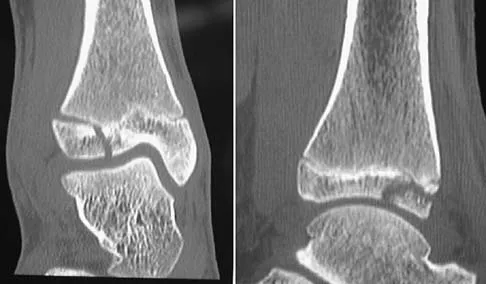

A 15-year-old boy reports leg pain after being tackled during football practice. Radiographs and a CT scan are shown in Figures 46a through 46c. The patient has a pathologic fracture through what underlying lesion?

Explanation

Figures 45a through 45c show the radiograph, CT scan, and MRI scan of a 15-year-old boy who has lateral ankle pain. What is the most likely diagnosis?

Explanation